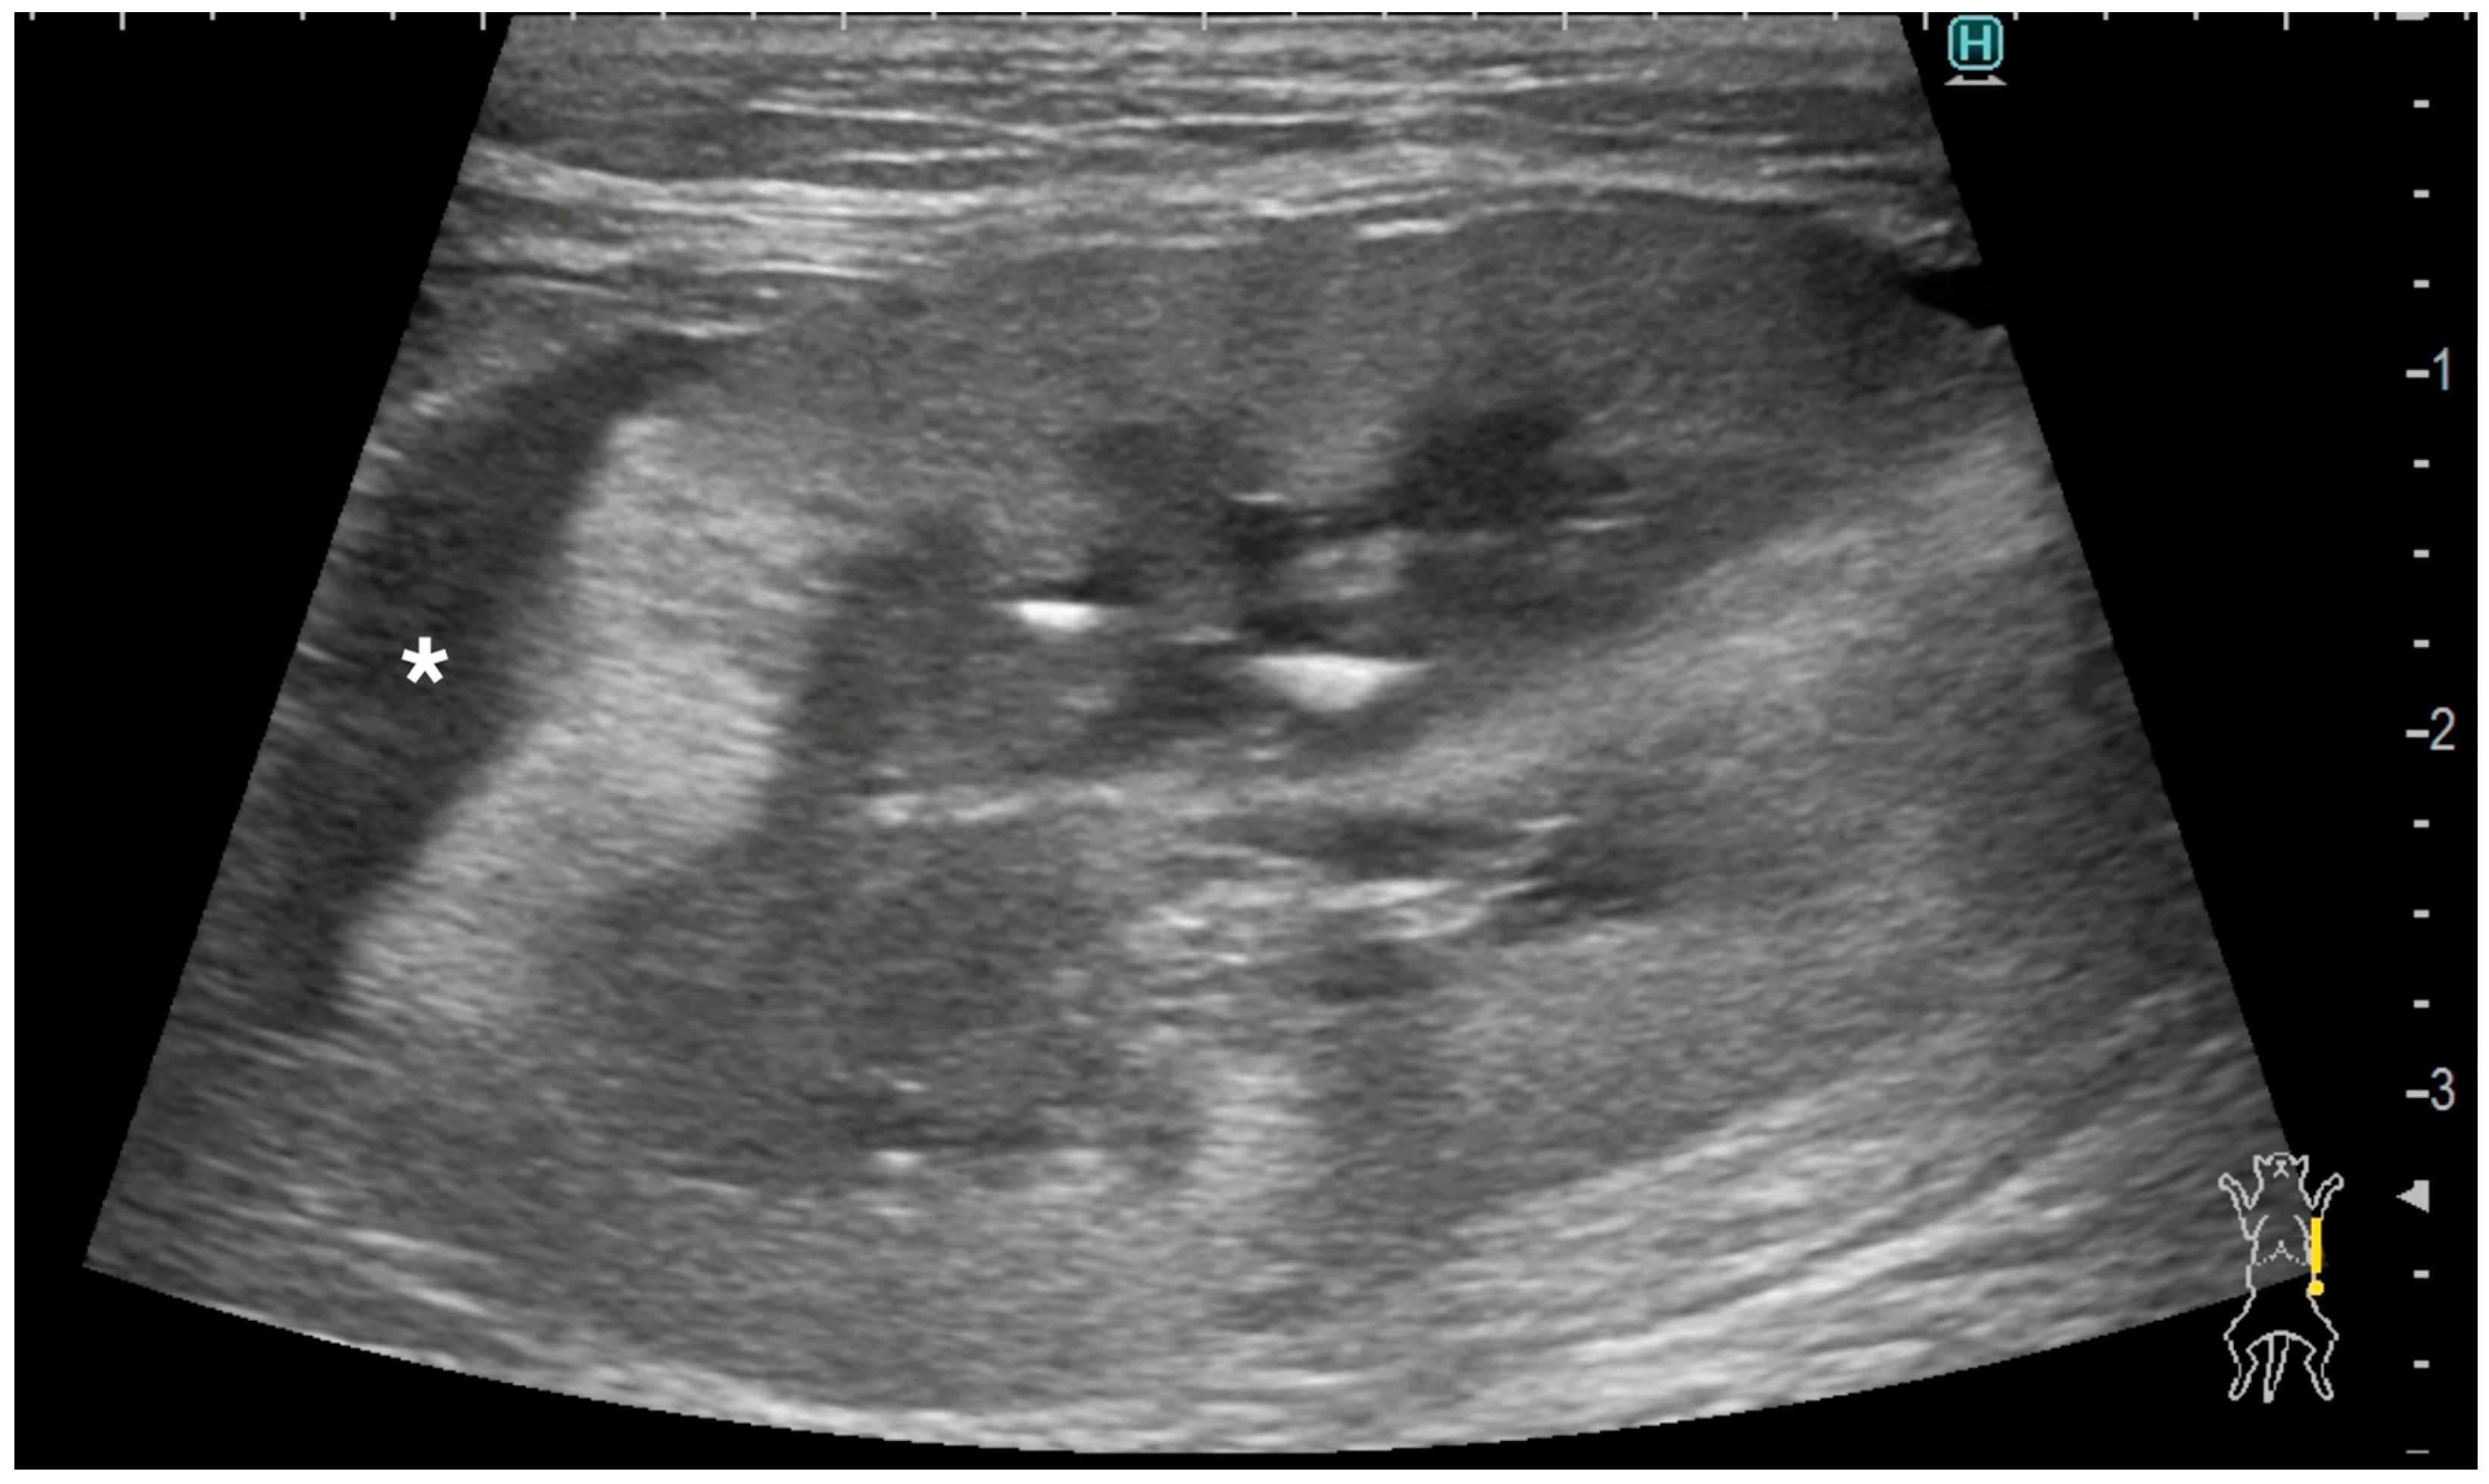

3.3. Ultrasonographic Findings of Subcapsular Thickening

3.4. Ultrasonographic Findings of the Rest of the Kidney

| 1 | 10 year-old, MN, DSH | left | focal | 3.5 | homo | hypo | irregular | irregular | no | no | normal | ill-defined | 1.3 | no | no | yes | Metastatic Carcinoma and Suspected Metastatic Carcinoma (sample obtained from either right or left kidney) | Pulmonary Carcinoma (lung, muscle) | |

| right | focal | 3.5 | homo | hypo | irregular | irregular | no | no | abnormal | hypoechoic striations within hyperechoic areas | ill-defined | no dilation | no | no | no | ||||

| 3 | 11 year-old, MN, DSH | right | focal | 2.8 | homo | hypo | irregular | smooth | yes | no | abnormal | ill-defined | no dilation | no | no | yes | Suspected Metastatic Carcinoma | Pulmonary Carcinoma (lung) | |

| 4 | 9 year-old, FN, DSH | left | focal | 4.8 | homo | hypo | irregular | irregular | no | no | abnormal | hypoechoic striations within hyperechoic areas | ill-defined | no dilation | no | no | no | Metastatic Carcinoma | Pulmonary Carcinoma (lung) |

| right | focal | 1.5 | homo | hypo | smooth | smooth | NA | no | abnormal | well-defined | no dilation | no | no | no | Suspected Metastatic Carcinoma | ||||

| 5 | 14 year-old, FN, DSH | left | focal | 1.2 | homo | hypo | smooth | smooth | NA | no | abnormal | hypoechoic striations within hyperechoic areas | ill-defined | no dilation | no | no | no | Metastatic Carcinoma | Pulmonary Carcinoma (lung) |

| 6 | 11 year-old, MN, DSH | left | focal | 3 | homo | hypo | smooth | smooth | NA | yes | normal | ill-defined | no dilation | yes | no | no | Metastatic Carcinoma | Metastatic Carcinoma (lung) | |

| right | circumferential | 13.2 | hetero | hetero | irregular | irregular | yes | yes | abnormal | completely effaced | 1.9 | yes | yes | no | Primary Renal Carcinoma | ||||